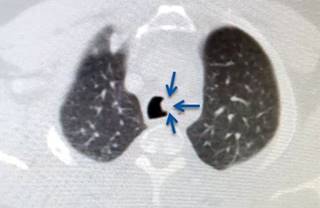

Se realizó resección de tráquea por toracotomía posterolateral derecha. El paciente requirió intubación selectiva del bronquio principal izquierdo para colapsar pulmón derecho. El abordaje fue por el cuarto espacio intercostal donde se disecó y ligó la vena ácigos para proceder a la disección de tráquea, por medio de broncoscopio se delimitó el área de resección tumoral (Figura 3). La disección abarcó los 3-4 anillos contenedores del tumor (Figura 4), dejando márgenes de 1 cm superior e inferior. Se procedió a anastomosis terminoterminal realizada con vycril 3-0 (poligactina 910) puntos simples separados y reforzada con pleura vascularizada y cianoacrilato. Para verificar la ausencia de fuga se realizó maniobra de Valsalva a 40 cm de H20.

Figura 3: Resección de tráquea. Se puede observar tumoración en el segmento superior (flechas blancas) y vena ácigos ligada lateral a la tráquea (flecha azul).